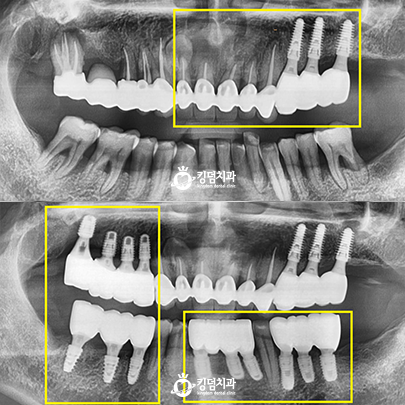

• 킹덤치과 전후사진

• 잇몸뼈 녹음, 2차 충치

• Before After

• 본 컬럼은 56조 제 1항의 의료법을 준수하여 작성되었으며 실제 내원 환자분의 동의하에 공개된 치료과정의 사진이 포함되어 있습니다.

개인에 따라 진료 및 치료방법이 다르게 적용될 수 있으며, 효과와 부작용이 다르게 나타날수 있는점을 안내 드립니다.